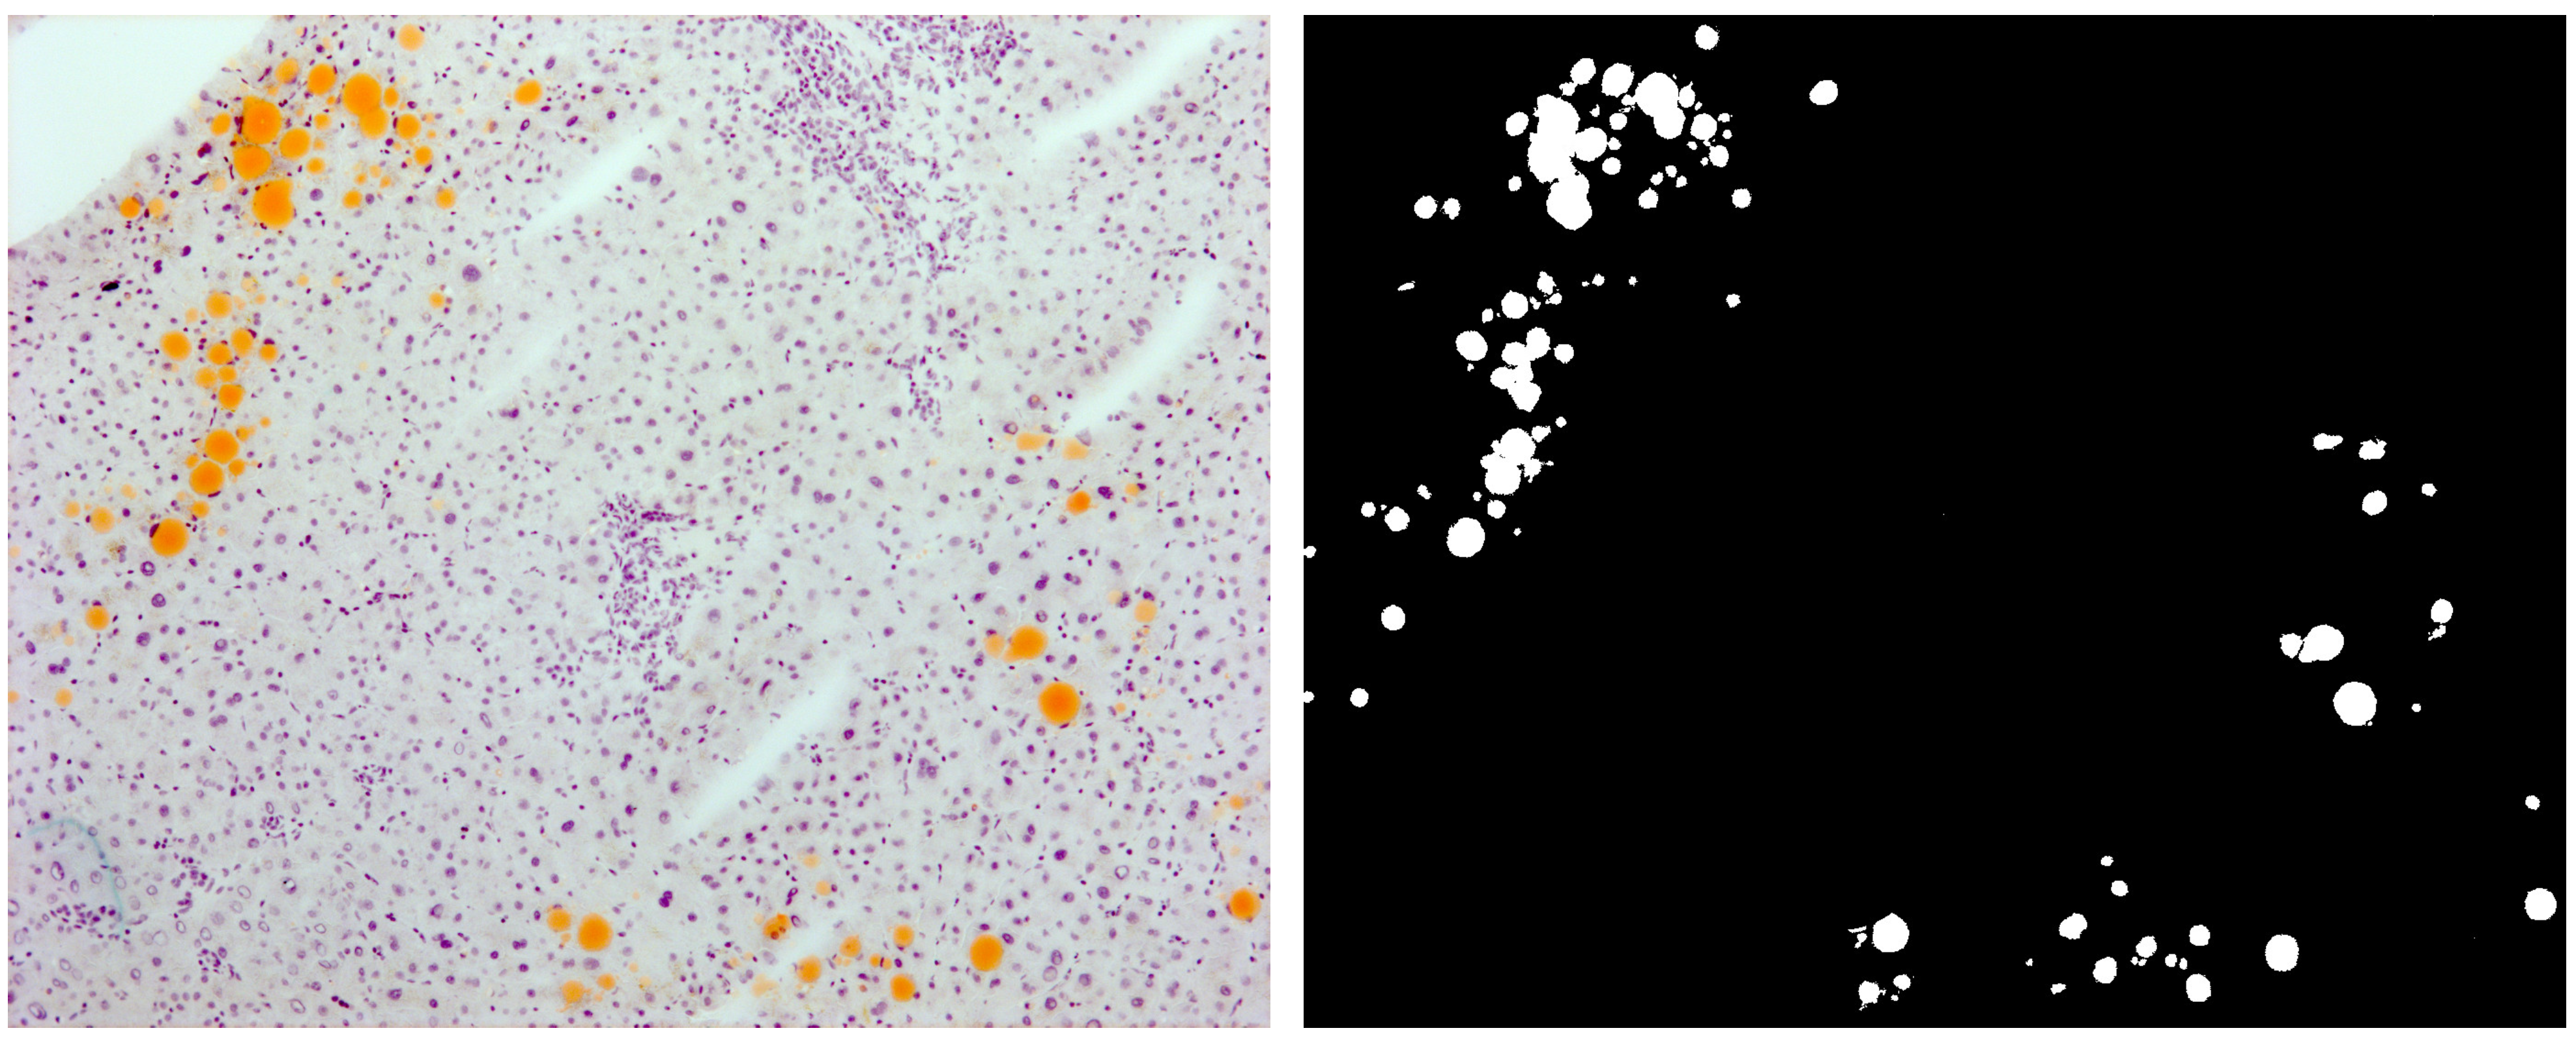

4.1. Liver Samples and Histochemical Procedures

4.2. Imaging